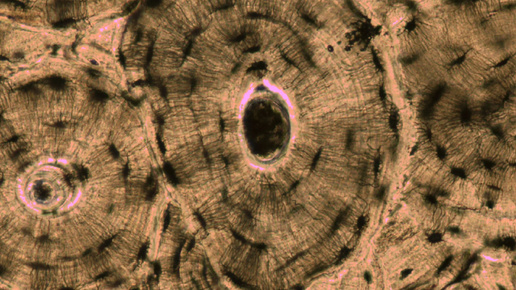

Прочность костной ткани зависит от множества факторов, таких как состав, соотношение элементов, и типа структурного компонента, что по сути делает костную ткань совершенно устроенным композитным материалом, параллельно выполняющим ещё множество других функции... Не будем далеко углубляться и приступим к изучению следующего понятия – компактная костная ткань. Компактная (кортикальная) костная ткань – является одним из двух основных типов костной ткани, наряду с губчатой (трабекулярной) костной тканью – которые формируют структуру костной ткани и кости в целом...

Опорно-двигательный аппарат (локомоторный) — костно-мышечный комплекс, состоящий из костей, их соединений и соматических (регулируемых нервной системой произвольно) мышц. Скелет (skeleton) — совокупность всех костей, связок и хрящевой ткани. Кость ( лат. os) — твёрдый орган, состоящий комплекса тканей, основной из которых является костная. Вещество кости представлено двумя видами: компактным и губчатым. Первое локализуется снаружи, второе — внутри. Компактное вещество значительно плотнее, тяжелее...